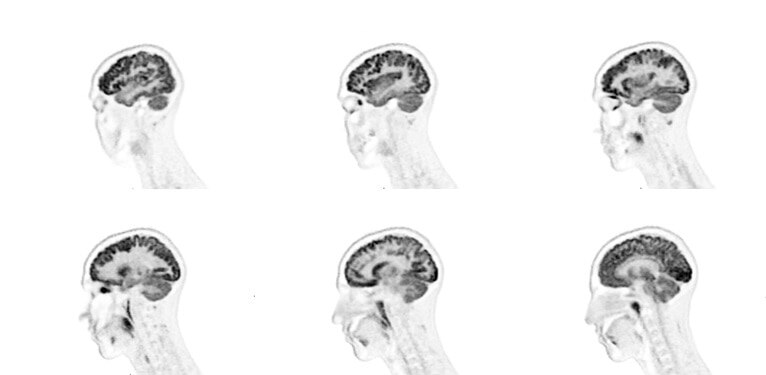

Seen here is a theranostics 18F-PSMA case, after prostate removal. There was suspected recurrence due to elevated markers. No pathological findings at the surgery area.

omni-legend-image-diagnostic-portion-ci-en

Able to image Gallium 68 for diagnosis, staging or restaging

This image is a theranostics 68Ga-PSMA case for prostate cancer assessment response to treatment. There were pathological findings in the lymph nodes in the pelvic area.